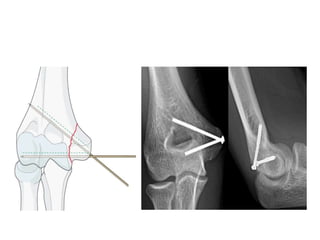

Measurements on Lateral Radiograph

1. Anterior Humeral- Capitellar Line.

2. Radiocapitellar Alignment.

3. Anterior Angulation of Articular Surface of Distal

Humerus.

4. Olecranon- coronoid angle.

5. Greater Sigmoid Notch Circle

Measurement technique for greater sigmoid notch angle